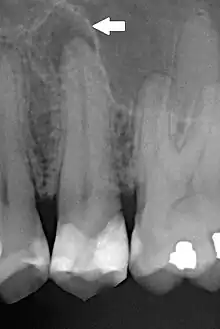

| Periapical dental radiograph showing chronic periapical periodontitis on the root of the left maxillary second premolar. Note large restoration present in the tooth, which will have undergone pulpal necrosis at some point before the development of this lesion. | |

Periapical periodontitis or apical periodontitis[1] (AP) is an acute or chronic inflammatory lesion around the apex of a tooth root, most commonly caused by bacterial invasion of the pulp of the tooth.[2] It is a likely outcome of untreated dental caries (tooth decay), and in such cases it can be considered a sequela in the natural history of tooth decay, irreversible pulpitis and pulpal necrosis. Other causes can include occlusal trauma due to 'high spots' after restoration work, extrusion from the tooth of root filling material, or bacterial invasion and infection from the gums. Periapical periodontitis may develop into a periapical abscess, where a collection of pus forms at the end of the root, the consequence of spread of infection from the tooth pulp (odontogenic infection), or into a periapical cyst, where an epithelial lined, fluid-filled structure forms.